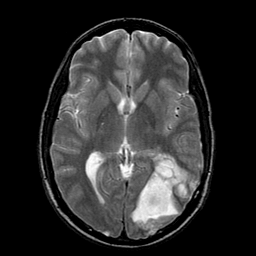

Sarcoma, MR Study #1 mr-t2 -- Slice #11

[Home][Help][Clinical] Slice 11